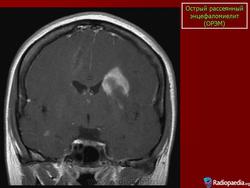

Основу патоморфологического процесса составляют периваскулярные множественные очаги демиелинизации с участием микроглии. Локализация процесса различна: белое вещество больших полушарий мозга, ствол мозга, спинной мозг. Периаксиальный демиелинизирующий процесс обнаруживается и в спинномозговых корешках и нервах конечностей.

Диагностика. Диагноз основывается на остром инфекционном начале, наличии симптомов мультифокального полисистемного поражения. Дифференцировать рассеянный энцефаломиелит следует от энцефаломиелитов при кори, ветряной оспе, краснухе. Основное значение при этом имеют данные анамнеза. Более сложен дифференциальный диагноз с рассеянным склерозом. В большинстве случаев окончательный диагноз устанавливается после длительного наблюдения. Наличие рецидивов и ремиссий свидетельствует о рассеянном склерозе.